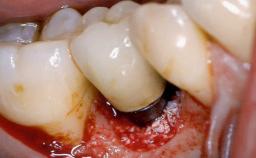

In this case, Nicola Zitzmann describes the sudden loss of a previously well-osseointegrated implant that had been in healthy function for 5 years. The case includes recommendations for occlusion and function of implant restorations. A 74-year-old patient had received implant-fixed dental prostheses in the maxilla in 2008, and in the right mandible three years later. His tooth loss was mainly related to recurrent caries associated with hyposalivation as a potential side effect of his cholesterol-lowering medication.